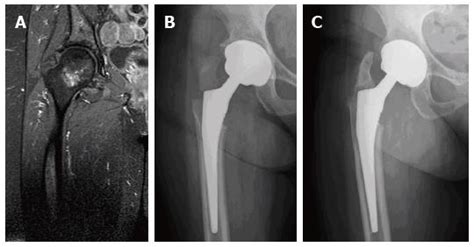

At radiography, the greater trochanter is displaced ultrasound and radiographic feature of an avulsion fracture of the lesser trochanter apophysis. Surgical fixation allows almost immediate mobility. In adults, the ligaments and tendons tend to be injured first, whereas in children the bone may fail before the ligament or tendon is injured. Avulsion fractures can happen anywhere in the body where soft tissue attaches to the bone. Milch h (1939) avulsion fracture of the great trochanter. It may be noted that these muscles aid in hip movement by joining to the greater trochanter. For children with 4 or more years of. John kiel on 26 september 2020 01:20:47. Blurry or hazy endplates, fracture line, line of impaction, step defect. Regardless of the treatment chosen, this pathology has a. At radiography, the greater trochanter is displaced ultrasound and radiographic feature of an avulsion fracture of the lesser trochanter apophysis. Intertrochanteric area exists between greater and lesser trochanters. Avulsion of the greater trochanter occurs when there is a sudden directional change (, 6,, 16 ). This can occur at the ligament by the application of forces external to the body (such as a fall or pull). An avulsion fracture is a bone fracture which occurs when a fragment of bone tears away from the main mass of bone as a result of physical trauma. In the pelvis, the newly formed secondary centers of ossification. A tension band wire technique is a good alternative for smaller fragments.